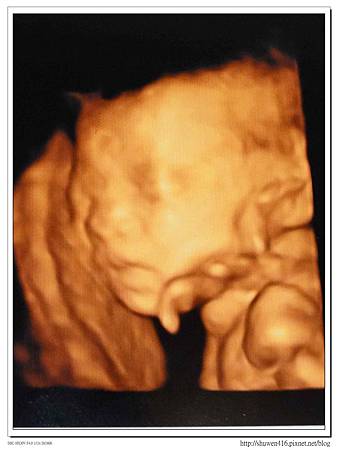

附上一張安寶寶的照片,這次醫生特別提到鼻骨部分比較尖挺且長,可能真的遺傳到安爸的大鼻子了!和之前安安的高層次照片相比,有沒有一些相似呢!